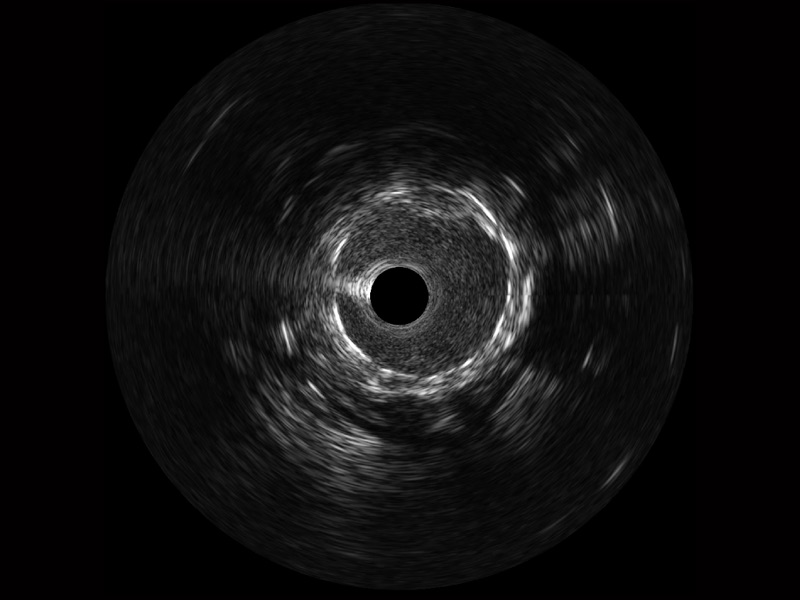

传统IVUS图像

对比传统IVUS导管成像,美狮贵宾会官网宽频IVUS图像的近场支架梁显影更细腻,远场中膜外血管仍清晰可辨,兼顾远中近,兼顾分辨力与穿透深度